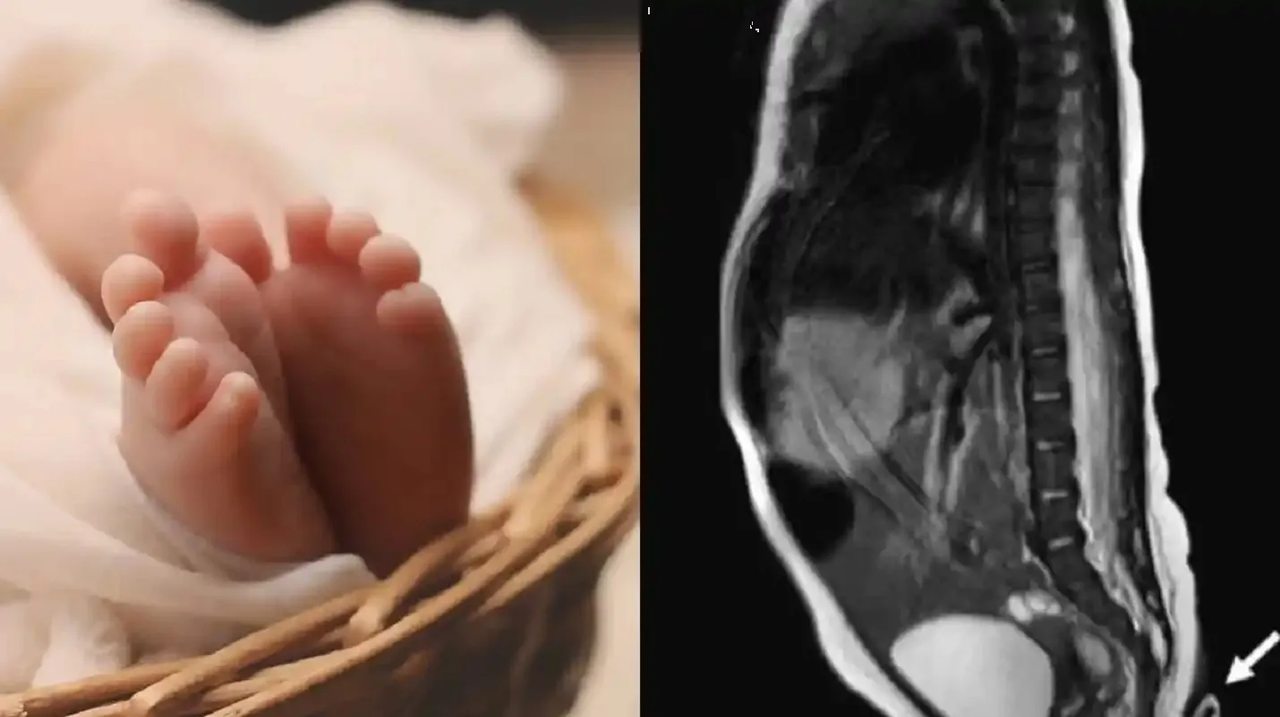

Debido a que el pequeño presentó una continuación de la columna vertebral que podría afectar su desarrollo, el neurocirujano Amarnauth Dukhi, la describió como un disrafismo espinal peculiar, por lo que tuvo que someterlo a cirugía a pesar de que solo teñía 10 días de nacidoAunque el procedimiento fue tardado, los especialistas lograron remover con éxito la sección sin afectar los elementos nerviosos involucrados, por lo que ahora el caso tendrá un seguimiento por parte del personal de la Corporación del Hospital Público para evaluar su evolución.

Este crecimiento extendido es caso de estudio en los mejores centros de salud del mundo, ya que solo hay 60 expedientes debidamente documentos y la base etiológica que provoca esta anomalía es desconocida, puesto que incluye la generación de meningocele, lipoma espinal y espina bifída oculta.